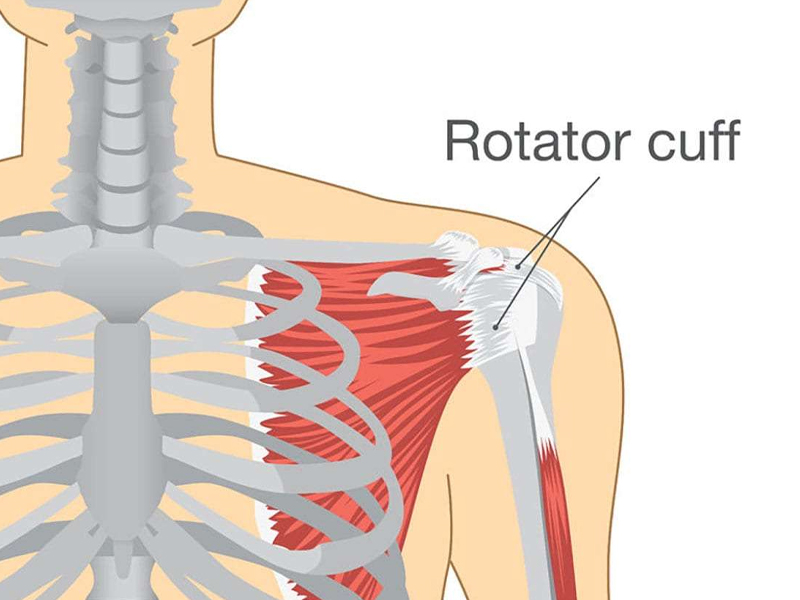

Shoulder arthroscopy (bankart repair, laterjet,frozen shoulder, rotator cuff

repair)

Rotator Cuff

A rotator cuff tear is a common cause of shoulder pain and disability among adults. Each year, almost ...